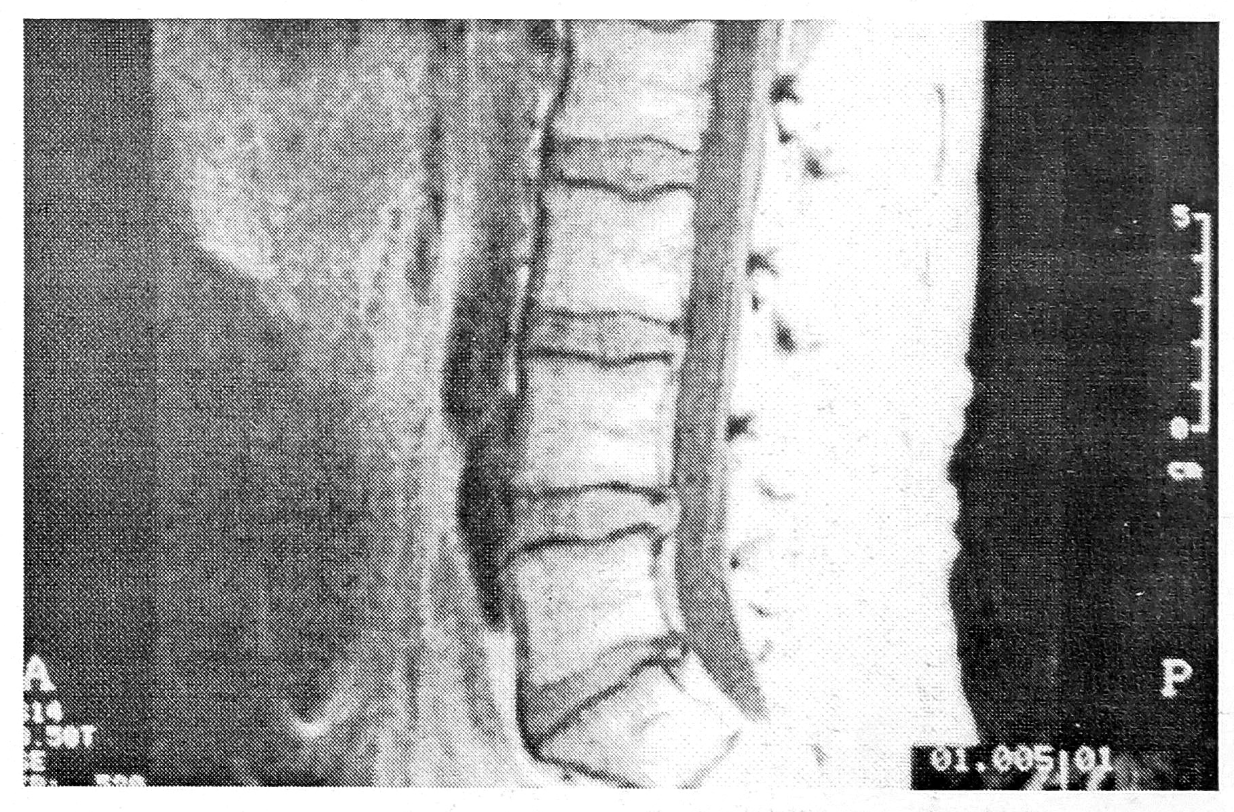

При поясничной остеохондропатии дегенеративные изменения в межпозвонковых дисках выявляются как при дискографии [38], так и на МР-томограммах [35]. Учитывая, что в ряде случаев характер структурно-функциональных изменений в диске имеет принципиальное значение для выбора лечебной тактики, следует уточнить показания к применению методов рентгенологического обследования.

Снижение интенсивности Т2 параметра МР- сигнала отражает биохимическую дегенерацию межпозвонкового диска, указывая на уменьшение содержания протеогликанов и дегидратацию студенистого ядра [41, 47]. В связи с этим MP-томография является наиболее чувствительным методом определения начинающейся дегенерации диска [16, 17, 24, 33, 35, 36, 40]. Между тем широкое применение этого метода поставило перед исследователями новые вопросы. Еще в 1989 г. Н. Paajanen и соавт. [35] отметили, что в ряде случаев сложно интерпретировать данные MP-томографии как дегенеративные изменения в диске или только как начало физиологических возрастных изменений. Иногда MP-томография дает ложноположительный результат [8, 25, 37]. С другой стороны, не менее часты и ложноотрицательные результаты, когда при дискографии выявляются дегенеративные изменения тех межпозвонковых дисков, которые на МР-томограммах выглядели здоровыми [6, 11, 18]. Кроме того, MP-сигнал, особенно Т2 параметр, может стимулировать компрессию нервных корешков [7].

Идеальным является использование МР-томографии для контроля за эффективностью консервативного лечения, а также сразу же после оперативного вмешательства. Контрольное MP-исследование нужно проводить не ранее чем через 6—8 нед после начала консервативного лечения, когда определяется достоверное уменьшение грыжевого выпячивания [12—15]. Кроме того, этот метод позволяет дифференцировать подсвязочные и секвестрированные грыжи дисков [26, 29, 42], что принципиально важно при выполнении хемонуклеолиза и чрескожной нуклеотомии.